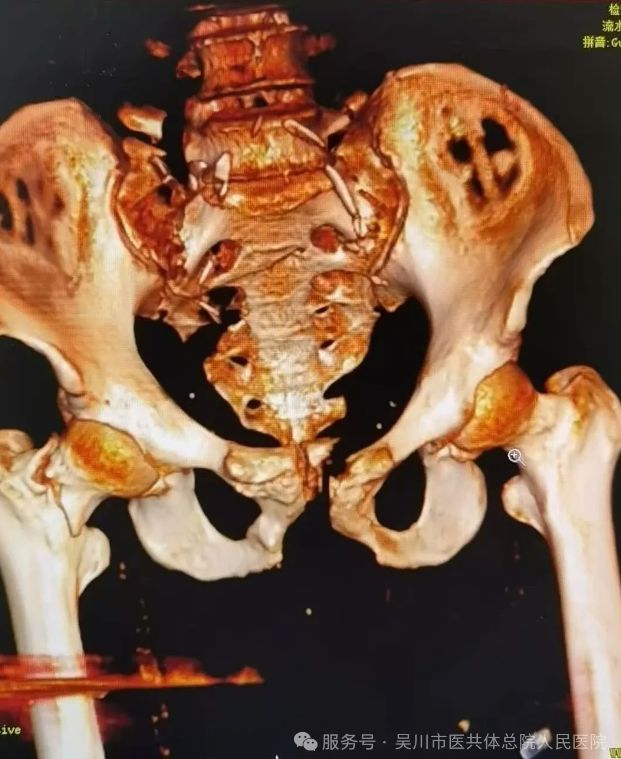

骨外科一区主任、主任医师李德强,立即带领专家团队对患者的各项身体指标、受伤情况等进行综合评估,缓解家属的焦虑情绪。最终决定为患者施行损伤控制手术,稳定患者的生命体征,待其血流动力学稳定后,再二期采用微创小切口的方式来修复骨盆以及股骨多段骨折。

这一技术是我院骨外科一区自主完成的创伤骨科中最高的四级手术之一,它的成功开展,意味着我院创伤骨科水平已达到三甲医院标准,彰显了我院在创伤救治领域深厚的专业底蕴和强劲的专业技术。